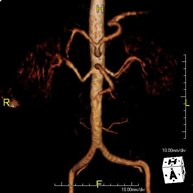

- Angio-RM Aorta abdominal

Prueba diagnóstica no invasiva que consiste en el estudio de la arteria aorta abdominal, obteniendo imágenes de alta definición anatómica mediante el empleo de un campo electromagnético y ondas de radio (con un emisor y un receptor). Es indispensable el uso de contraste paramagnético (Gadolinio). Sin embargo, no utiliza radiación ionizante. La calidad de las imágenes permite realizar reconstrucciones en 2D y 3D. Está indicado en aquellos pacientes con enfermedad vascular (aterosclerosis), estudio de aneurismas, en estudios pre-quirúrgicos de lesiones adyacentes a la aorta abdominal como "mapa" vascular, etc.

- Angio RM Aorta-ilíaca

Prueba diagnóstica no invasiva que consiste en el estudio de la arteria aorta abdominal de las arterias ilíacas, obteniendo imágenes de alta definición anatómica mediante el empleo de un campo electromagnético y ondas de radio (con un emisor y un receptor). Es indispensable el uso de contraste paramagnético (Gadolinio). Sin embargo, no utiliza radiación ionizante. La calidad de las imágenes permite realizar reconstrucciones en 2D y 3D. Esta prueba está especialmente indicada como estudio pre-quirúrgico (mapa vascular) antes de intervenciones percutáneas o quirúrgicas de aorta abdominal y arterias ilíacas, estudio complementario en pacientes con isquemia de miembros inferiores, etc.